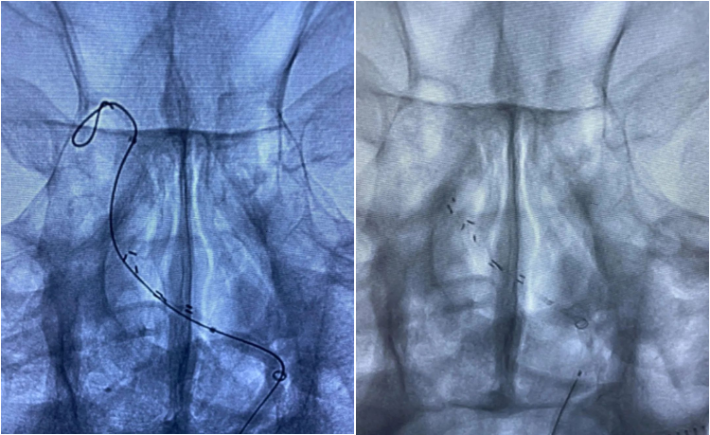

患者SCY,M59Y。2020年07月06日患者因症状性基底动脉重度狭窄,在外院行球囊扩张支架植入术。术中应用2.0mmx15mm Gateway球囊扩张,植入Enterprise 2 4.0mmx23mm支架,术后狭窄改善良好,患者无不适。规范应用双联抗血小板聚集治疗。

2020.07.10晚,患者术后第4天逐渐出现意识迷糊,嗜睡,考虑支架闭塞可能。遂急诊造影示:支架内血栓闭塞,意识模糊,危在旦夕,外院兄弟果断尝试再通,导丝导管通过后血流线样再通,撤回微导管注射替罗非班,血流难以维持。

再次尝试通过导丝导管,支架移位变形严重。

经过尝试,支架导管Rebar 18➕Synchro导丝200cm通过变形严重的原支架Enterprise 2。

打开取栓支架。

Solitaire AB 4mmx20mm成功挂住Enterprise 2。